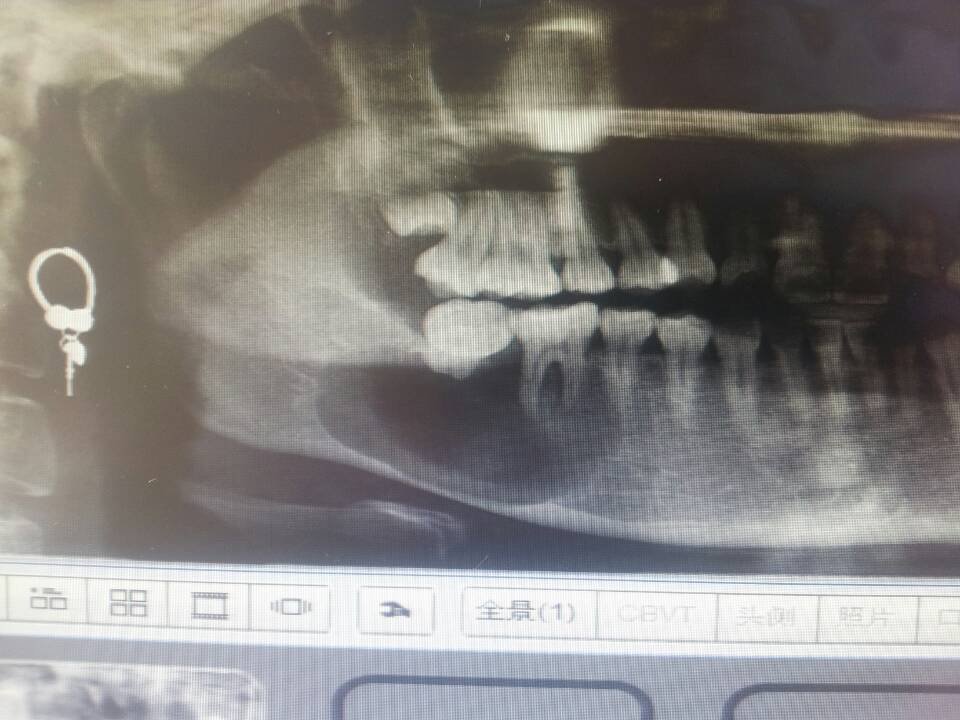

昨天去口腔医院检查牙齿,拍片发现牙齿下面长了个囊肿,医生说需要手术,但是我现在是哺乳期,孩子太小还 昨天去口腔医院检查牙齿,拍片发现牙齿下面长了个囊肿,医生说需要手术,但是我现在是哺乳期,孩子太小还不能断奶。我想知道,除了手术还有没有其他的治疗方法,等孩子大点了再手术。 点击展开 匿名用户 2014-09-07 11:55 为您推荐: 其他回答 手术和哺乳没关系,又不用住院,建议早治疗早康复 匿名用户 2014-09-07 12:04 做手术先 匿名用户 2014-09-07 12:00 囊肿越早治疗越好,拖长了容易病变 匿名用户 2014-09-07 11:59 不能 匿名用户 2014-09-07 11:58 相关问题 我家宝贝的牙齿开始发黑了 不会的,宝宝的牙齿可能是龋坏了,去口腔医院检查吧 啊~生孩子的时候没注意卫生,弄得现在牙齿很黄,想去做美白,有妈妈知道广州哪家口腔医院做牙齿美白好不? 成都有哪些矫正牙齿的医院,成都口腔医院周六上班吗?